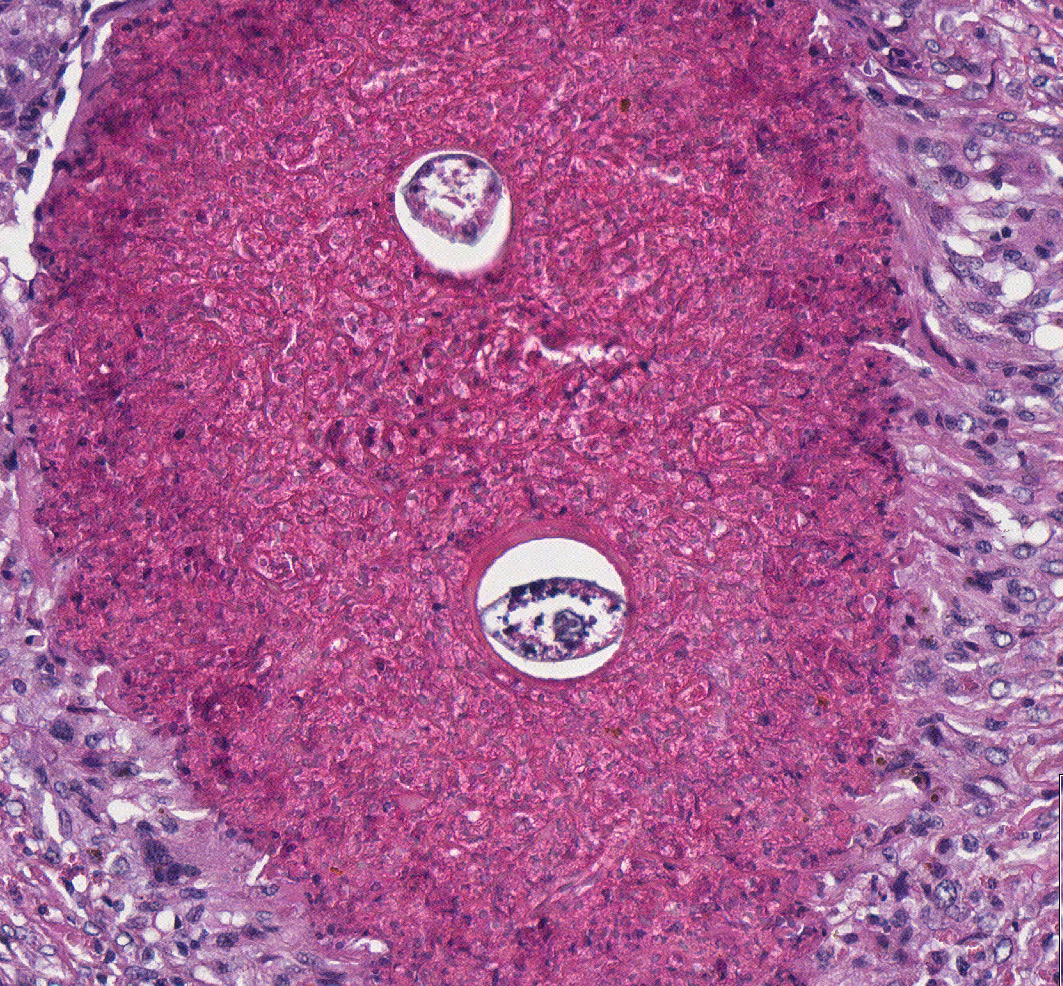

9

Q

What is the duration of this inflammatory process?

A

Chronic

What is the best modifier to describe the inflammatory exudate in the inflamed penis and urethra with Habronema L3 larval migrans

Granulomatous

Write an etiologic diagnosis for changes present in this sample.

Habronema